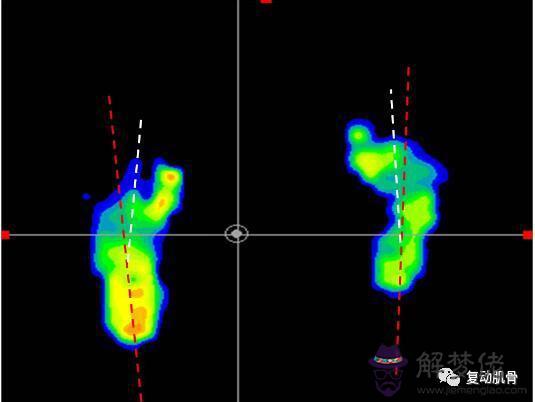

(三)跖骨內翻

又稱為前足內收,如下門診患者檢測結果所示,前腳掌偏離了足的行進線方向,而向內側偏斜,這種情況需要矯正鞋配合對前足進行外展牽拉,就能起到良好的矯正效果。

1.腳的前半部分相對于后半部分是向上、向內側偏移,造成內足弓上的皮膚折痕,從腳底看,腳的形狀像一個“C”。

2.可能與下肢旋轉問題(脛骨內旋)有關,第一和第二腳趾之間的空間過大。

腳外側突出的骨頭(第五跖骨),同時根骨出現內翻。

1.確定問題的程度(腳、腳踝或腿)和腳的靈活性,檢查相關肌肉是否出現失衡。

2.定制矯形鞋墊。

通過一雙全定制的矯正鞋墊來調整足部的生物力線,限制過度的內旋,提醒和限制小朋友的內八字步態。

情況嚴重的,夜間也需要定制一款“內八字夜用外展支具”固定矯正。

通過3D掃描設備,數據化測量,得到的數據報告直觀反映出兒童足部各種異常情況。